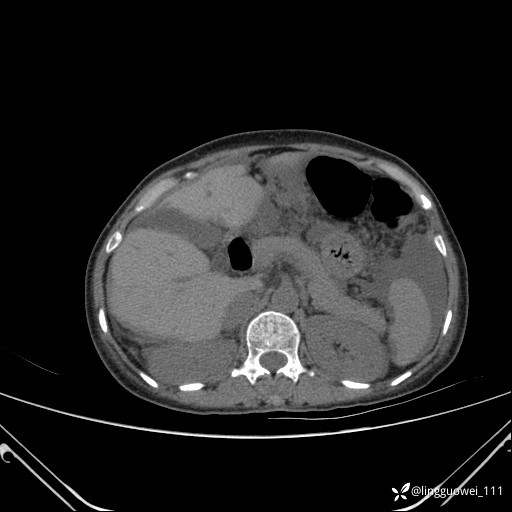

病例女,65岁,门诊行胃肠镜检查后,说腹胀入院检查,CT能发现病因吗?已公布结果

主诉:门诊行胃肠镜检查后,诉腹胀,入院检查,肝有病变吗?腹膜及腹腔的表现有特征性吗?

增强动脉期: